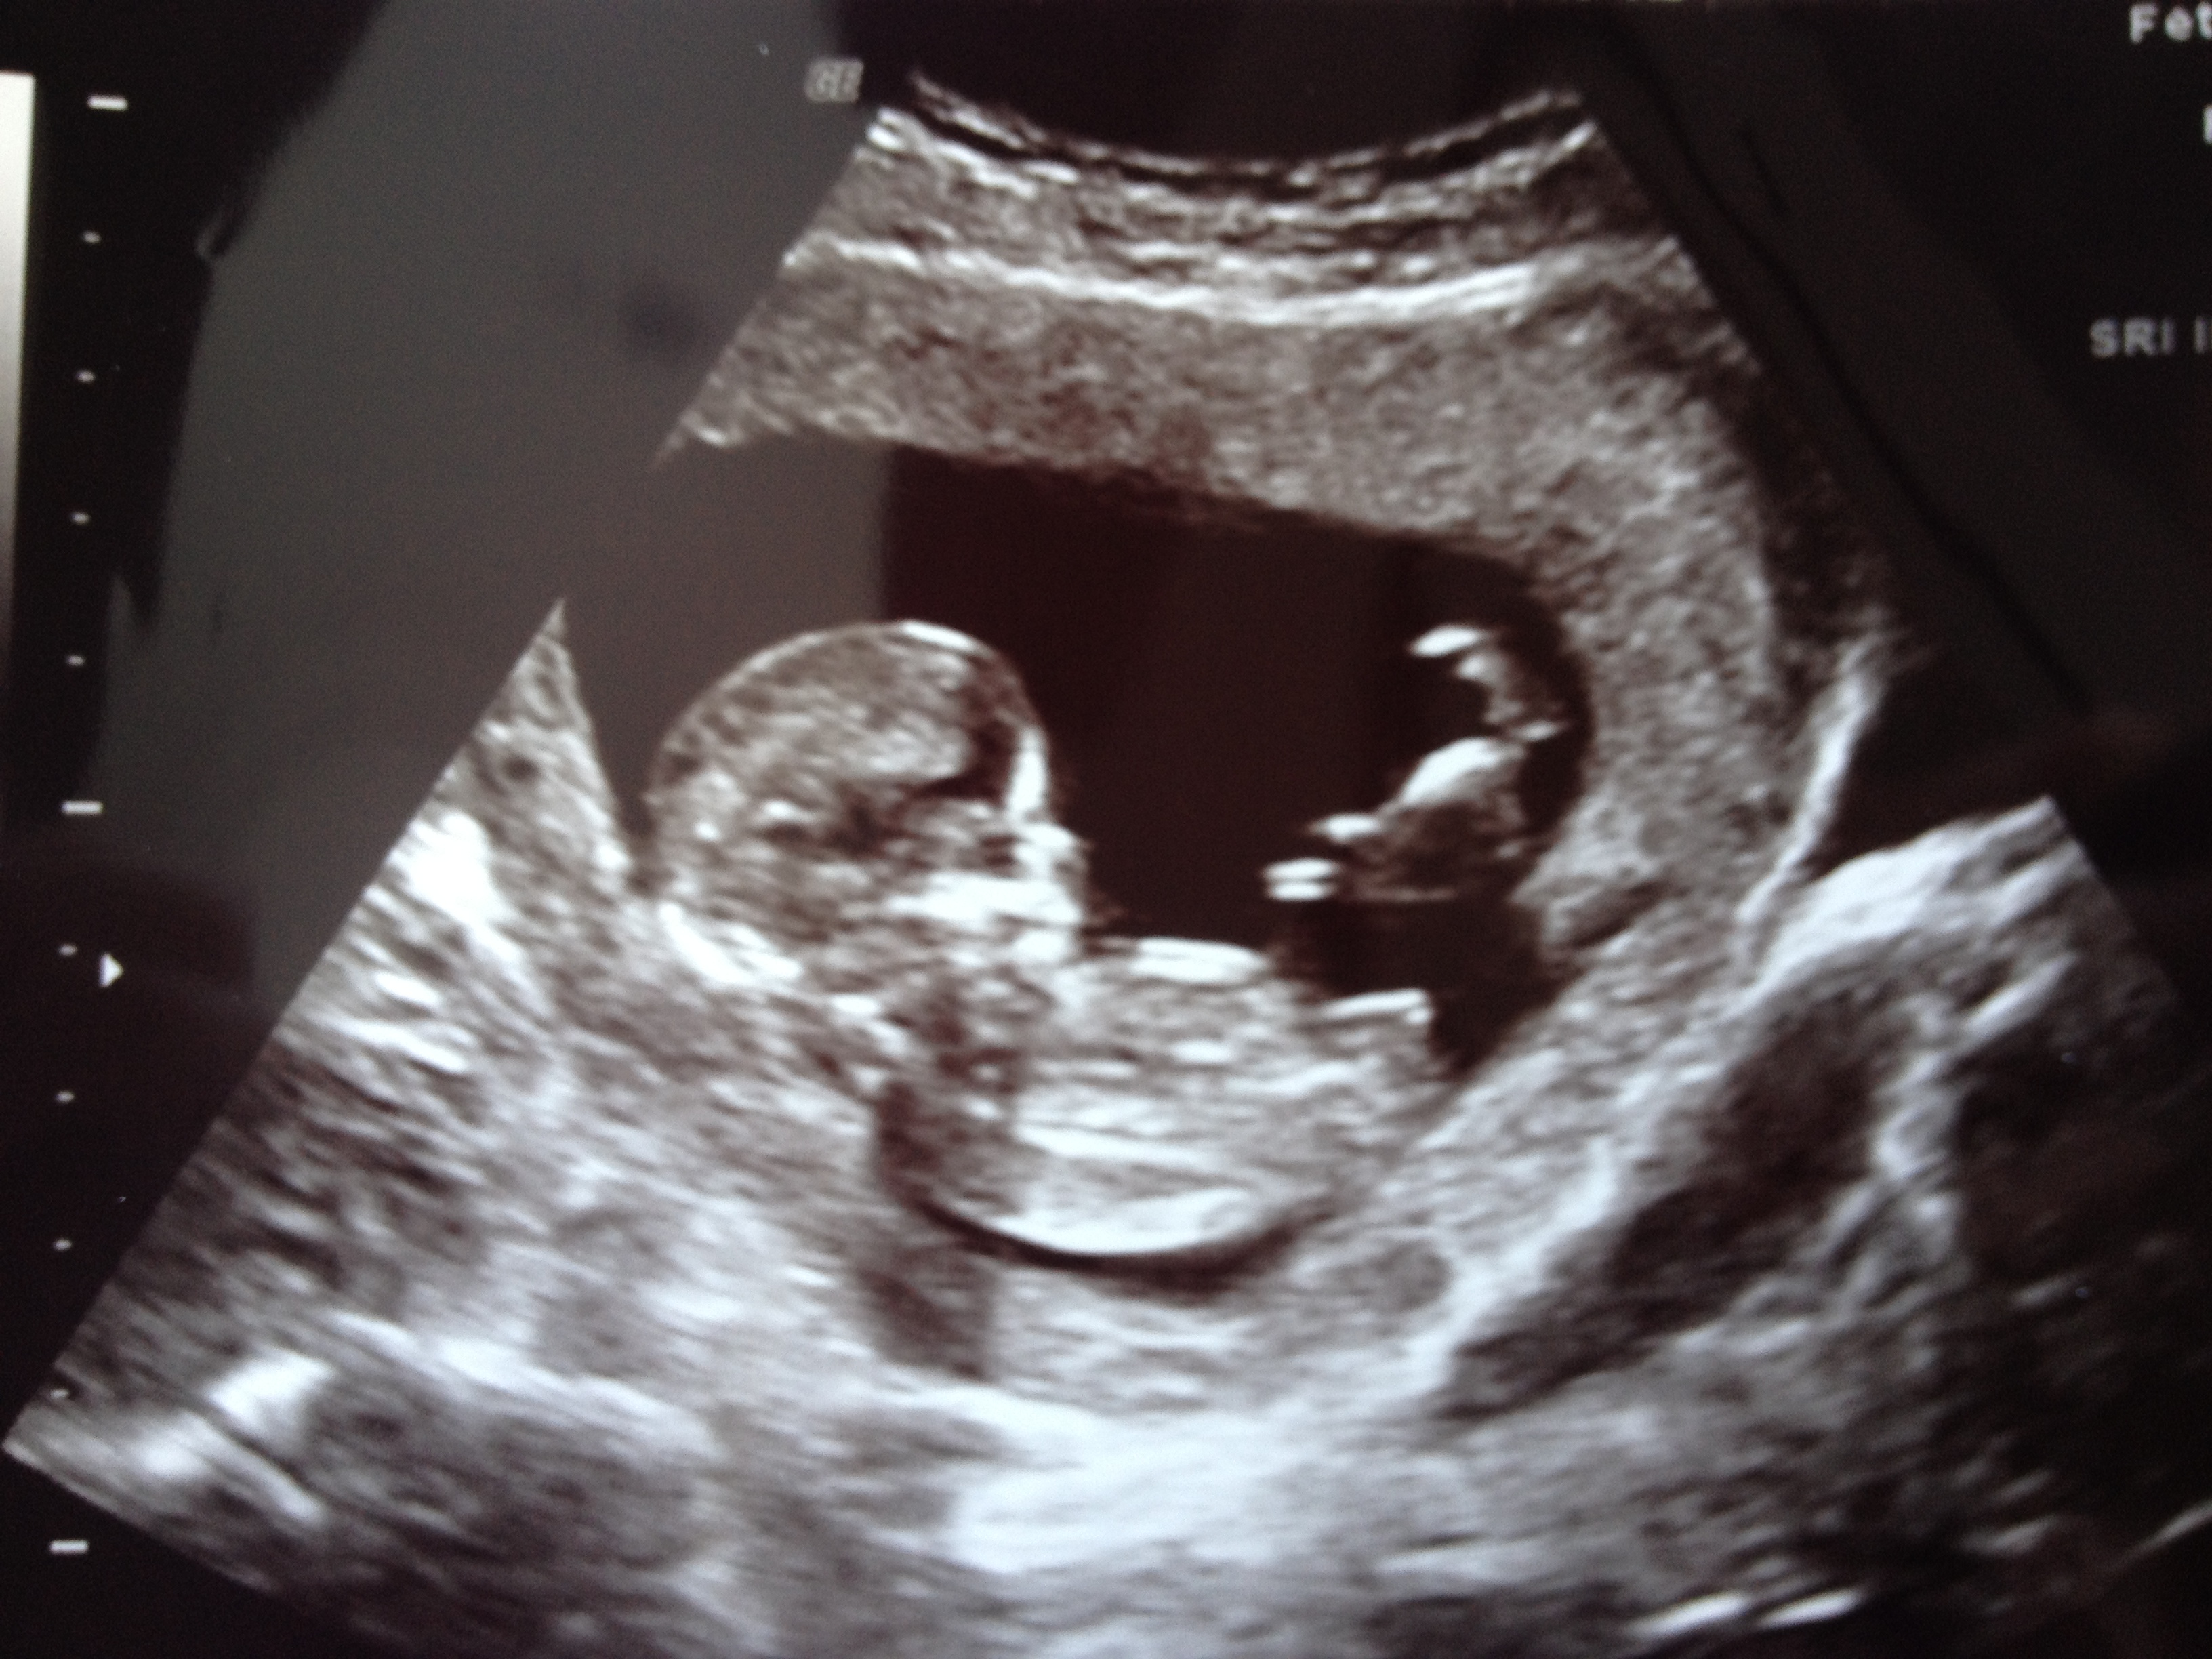

Maybe girl!!! GL what are you hoping for?

girl lean.

Hmmm. Baby is really curled. But nub looks girly in current position. I would lean girl.

I'm going girl guess

Im going girl on this one too x